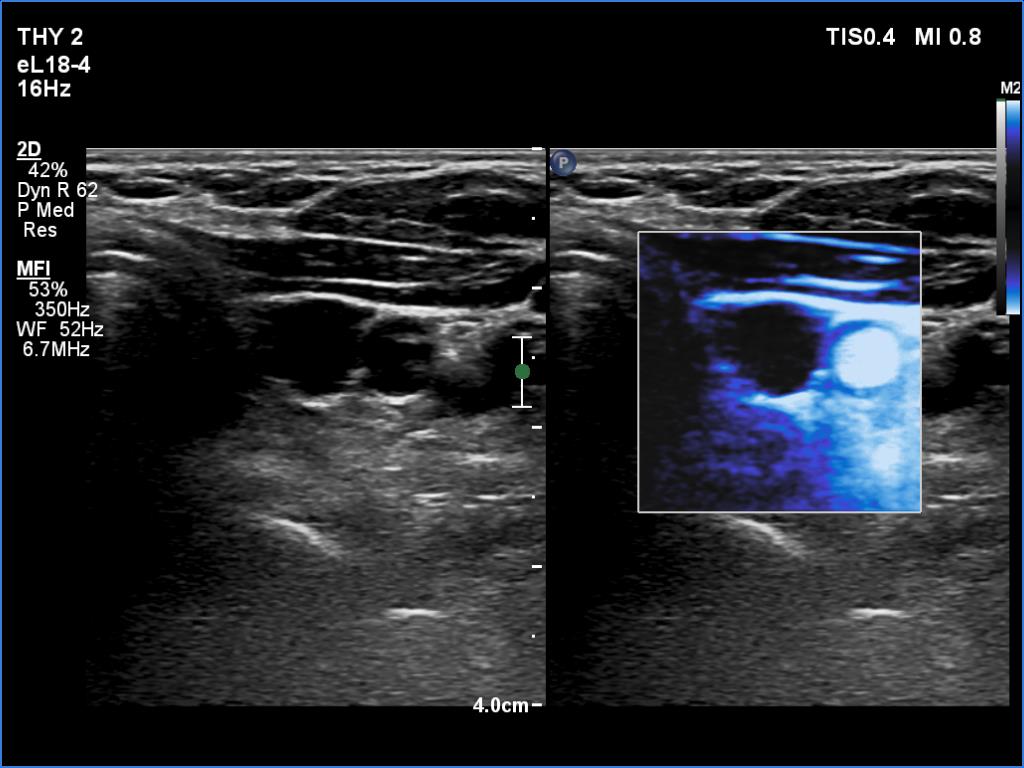

Right lobe, longitudinal scan

Left lobe, transverse scan, microflow imaging. The cyst does not have vessels.